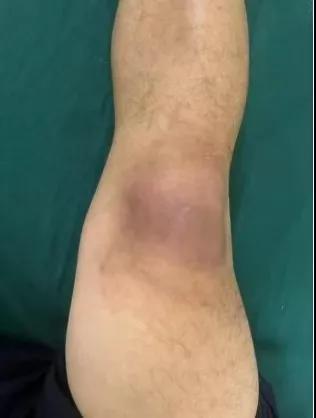

近日,漯河醫(yī)專二附院(漯河市骨科醫(yī)院、漯河市立醫(yī)院)手顯微外科(骨四科)李俊明主任團隊?wèi)?yīng)用清熱解毒、拔毒生肌類中藥(骨炎膏)外用結(jié)合抗生素成功治愈一例膝關(guān)節(jié)外傷后軟組織感染病人。

患者,以“外傷致右膝紅腫、疼痛20余天”為主訴就診,20余天前,因騎電車摔傷右膝關(guān)節(jié),致使出現(xiàn)右膝腫脹、疼痛、活動受限,在當(dāng)?shù)蒯t(yī)院給予消腫、止痛治療效果差,繼而出現(xiàn)膝關(guān)節(jié)紅腫熱痛癥狀,門診給予滑膜炎片及消腫止痛藥物治療癥狀未見好轉(zhuǎn),慕名前來我院手顯微外科住院。入院當(dāng)天即給予中藥外敷(骨炎膏),穿刺膿性分泌物送細菌培養(yǎng),給予廣譜抗生素治療(細菌培養(yǎng)未出)。

中藥外敷(骨炎膏)主要適用于局部紅腫熱痛,四肢血栓形成、靜脈炎等,具有清熱解毒,拔毒生肌的作用。

中藥外敷骨炎膏給藥直接作用于病灶,彌補了單純口服藥物局部濃度不足的缺陷;同時,中藥外敷與抗生素的系統(tǒng)性抗感染形成"靶向-全身"雙重干預(yù),可顯著縮短療程并降低耐藥風(fēng)險,更為中西醫(yī)結(jié)合治療軟組織感染提供新的思路。(盧 闖 賈煒煒 劉 旭 袁錦鈺)